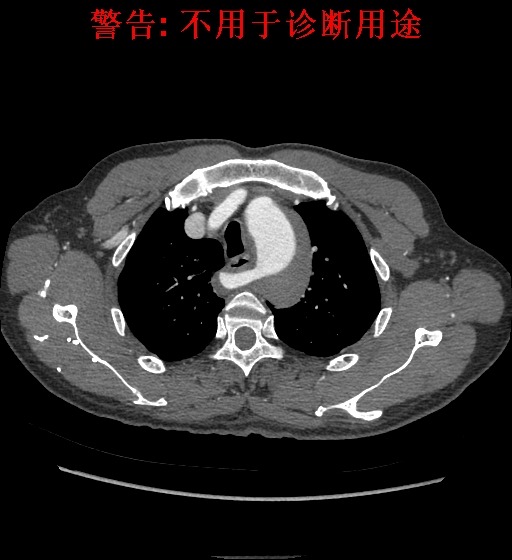

典型征象

CT 平扫见气管右侧类圆形结节影,易误诊,但连续层面观察见类圆形结节行走于食管后方,少数行走于食管气管间或气管前,往右上方走行向腋窝方向延伸;

CT 血管造影见迷走右锁骨下动脉起始于主动脉弓或降主动脉;

MIP 冠状位显示主动脉弓下缘“象鼻样”发出的血管,常由左下向右越过中线向上延伸,轴位则常为“鸟嘴样”改变。

诊断:B型主动脉夹层、主动脉壁间血肿、迷走右锁骨下动脉。

诊断:B型主动脉夹层、高血压、迷走右锁骨下动脉。

诊断:主动脉夹层,壁间血肿。